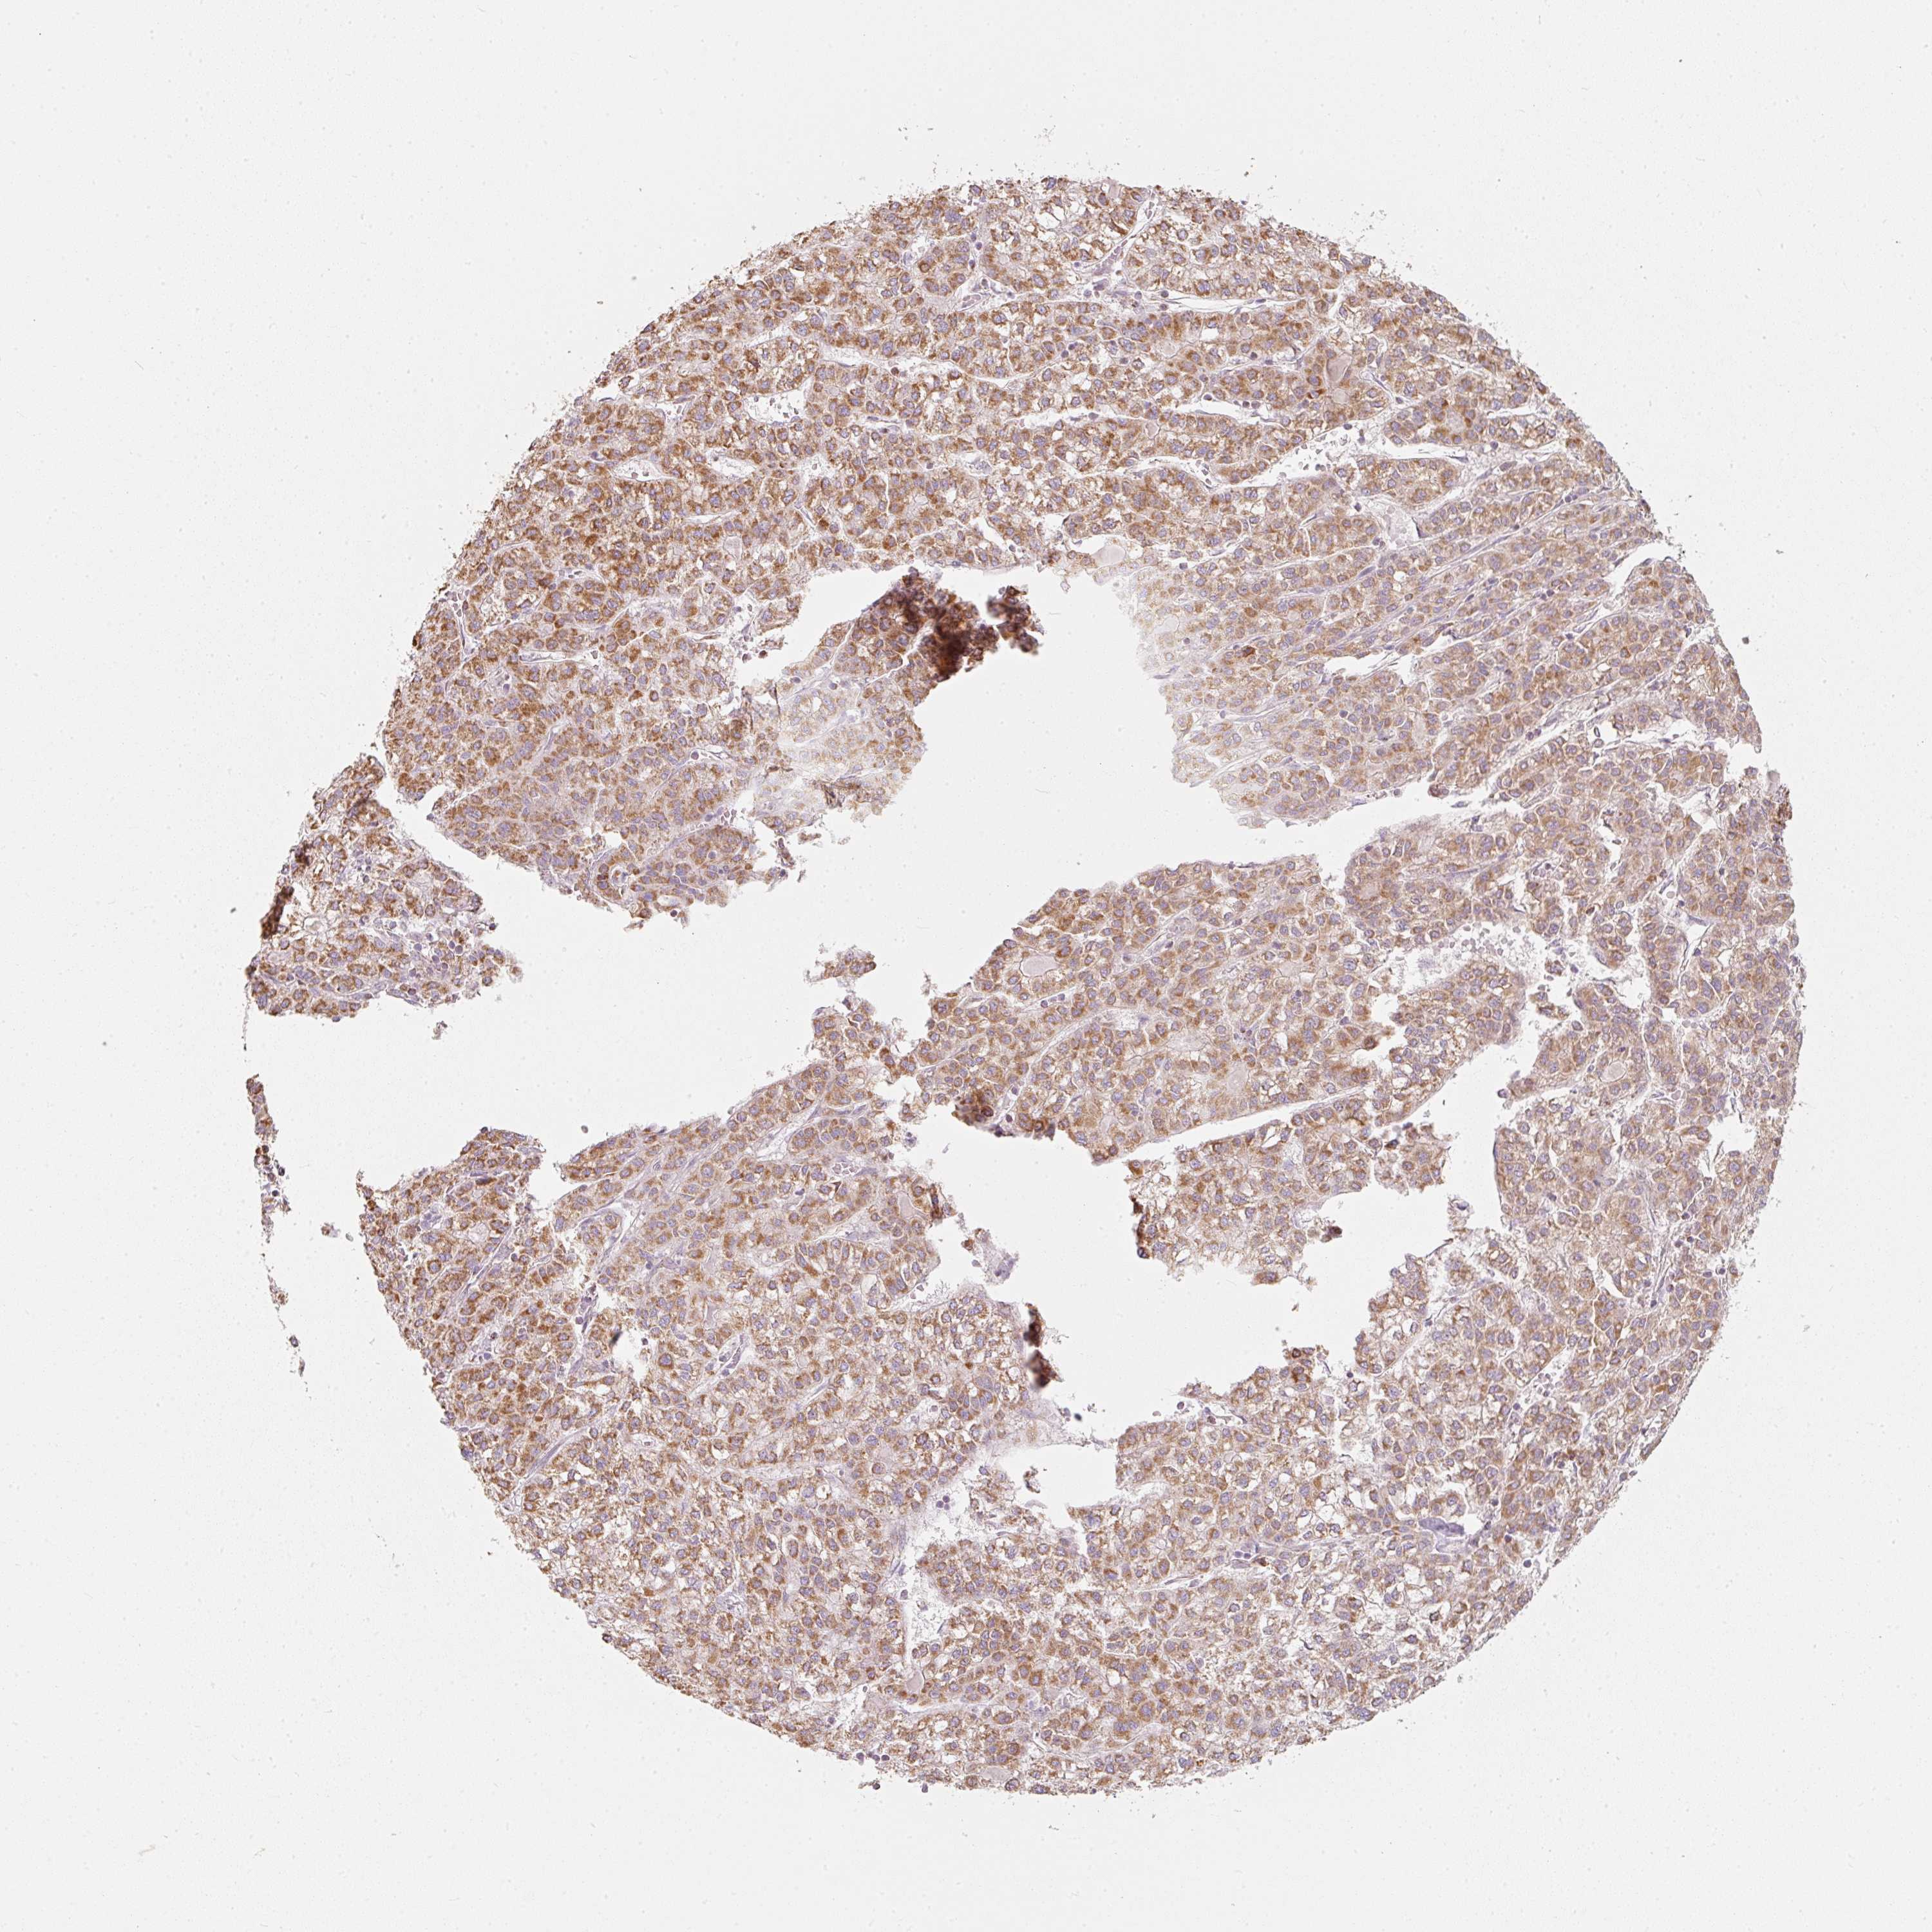

LIVER CANCER - Protein expressioni

A mouse-over function shows sample information and annotation data. Click on an image to view it in a full screen mode. Samples can be filtered based on level of antibody staining by selecting one or several of the following categories: high, medium, low and not detected. The assay and annotation is described here.

Note that samples used for immunohistochemistry by the Human Protein Atlas do not correspond to samples in the TCGA dataset.

Antibody stainingi

Antibody staining in the annotated cell types in the current human tissue is reported as not detected, low, medium, or high, based on conventional immunohistochemistry profiling in selected tissues. This score is based on the combination of the staining intensity and fraction of stained cells.

Each image is clickable and will lead to virtual microscopy that enables deeper exploration of all samples and also displays staining intensity scores, fraction scores and subcellular localization as well as patient and tissue information for each sample.

Antibody HPA054422

Antibody HPA060360

Staining

High

Medium

Low

Not detected

Intensity

Strong

Moderate

Weak

Negative

Quantity

>75%

75%-25%

<25%

None

Location

Nuclear

Cytoplasmic/membranous

Cytoplasmic/membranous,nuclear

Carcinoma, Hepatocellular, NOS

Cholangiocarcinoma